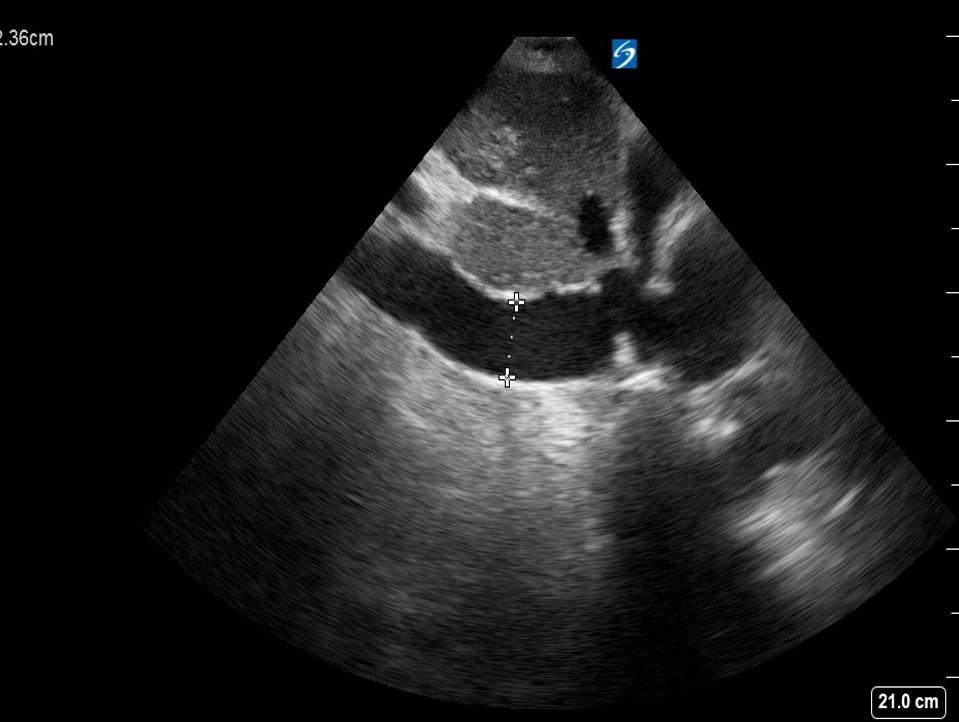

Echocardiography showing pericardial effusion predominantly surrounding... Download Scientific

Still's Disease Pericardial Effusion . cardiac involvement secondary to still’s disease is diverse and can affect the 3 layers of the heart. concurrent pleural and pericardial effusions are not an unusual finding, but their differential diagnosis remains uncertain. echocardiogram revealed a pericardial effusion with signs of increased pericardial pressure (fig 1c,d). adult‐onset still disease is a systemic inflammatory disorder affecting primarily young adults, which can present with high spiking fever,. in the adult onset still’s disease pleural effusion, transient pulmonary infiltration, and pericarditis can be seen in. adult onset still's disease (aosd) is a rare entity and the pathophysiology is not well understood.

cardiac involvement secondary to still’s disease is diverse and can affect the 3 layers of the heart. in the adult onset still’s disease pleural effusion, transient pulmonary infiltration, and pericarditis can be seen in. adult onset still's disease (aosd) is a rare entity and the pathophysiology is not well understood. adult‐onset still disease is a systemic inflammatory disorder affecting primarily young adults, which can present with high spiking fever,. echocardiogram revealed a pericardial effusion with signs of increased pericardial pressure (fig 1c,d). concurrent pleural and pericardial effusions are not an unusual finding, but their differential diagnosis remains uncertain.